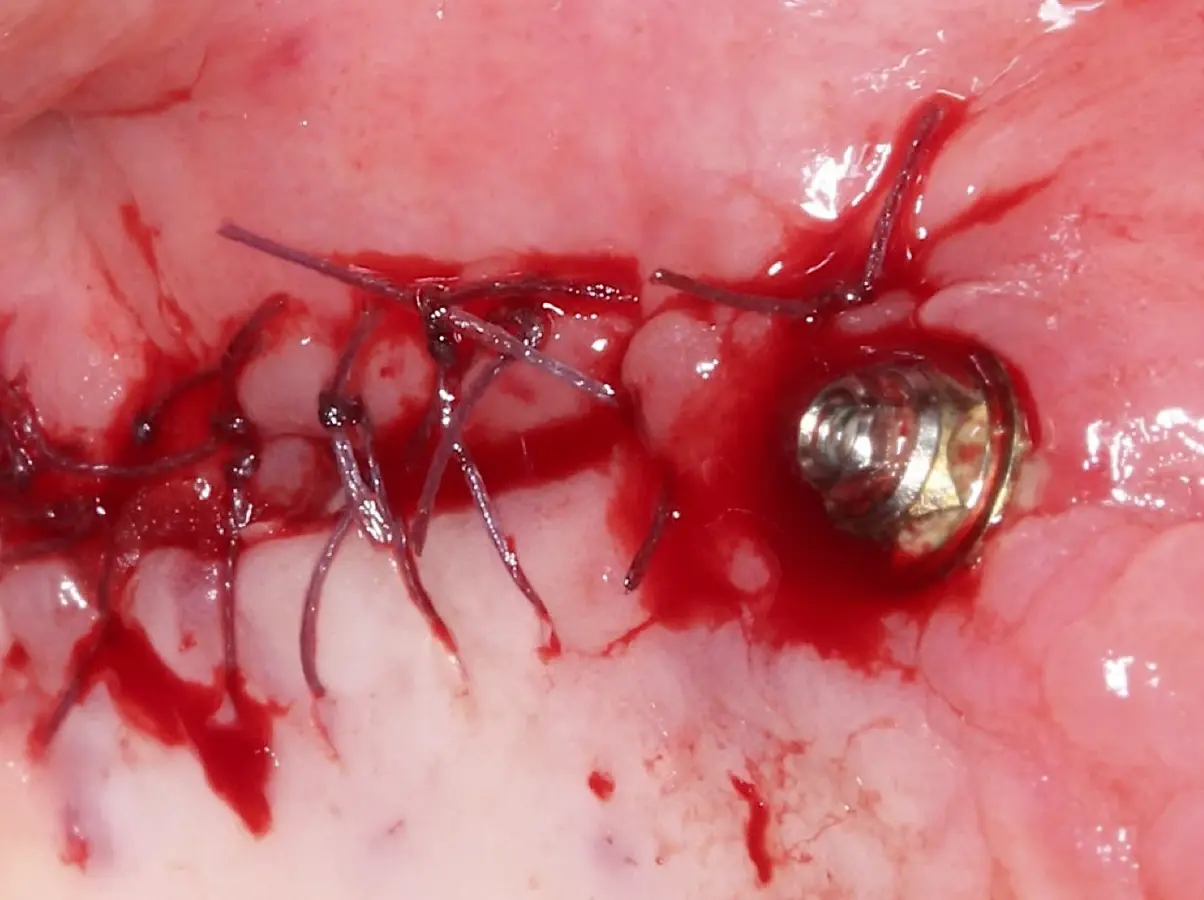

La técnica se inicia con la colocación de anestesia infiltrativa, posteriormente se realiza una incisión crestal o paracrestal con posibles liberantes verticales que deben de estar alejadas por lo menos 5 mm de los límites de la futura ventana y sobrepasar la línea mucogingival. Se realiza una elevación de colgajo, se inicia la antrostomía y antroplastía. Para ello, se emplea el inserto redondo diamantado de corte al momento de delimitar los bordes de la ventana de acceso. Luego se cambia al inserto aserrado liso de calibre fino con superficie diamantada, para profundizar y eliminar el hueso en el contorno de la ventana. Una vez que se traslucen los tejidos, se puede optar por el retiro de la tapa ósea o el levantamiento de ésta junto con la membrana.

Una vez elevado el piso sinusal según la planificación se realiza la evaluación clínica de la integridad de la membrana y de posibles desgarros a través de la maniobra de Valsalva.24 Consiste en pedir al paciente que respire profundamente y retenga el aire, cerrar la boca, apretar la nariz con los dedos y forzar la salida de aire. Al final de la prueba, es necesario mantener la presión entre 10 a 15 segundos. Se identificará la movilidad de la membrana y la ausencia de burbujas de aire para corroborar que no hay perforaciones. Dependiendo de la decisión clínica se puede optar por adicionar en la superficie de la membrana de Schneider membranas de colágeno o de plasma rico en fibrina (PRF) para dar mayor soporte durante la inserción del biomaterial de relleno óseo (Figura 10).